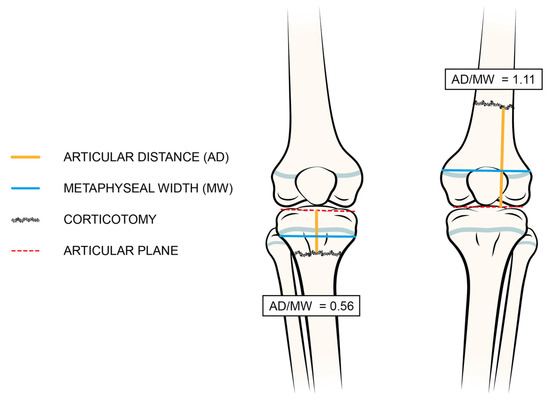

3.2. Radiographic Pre-Operative Variables